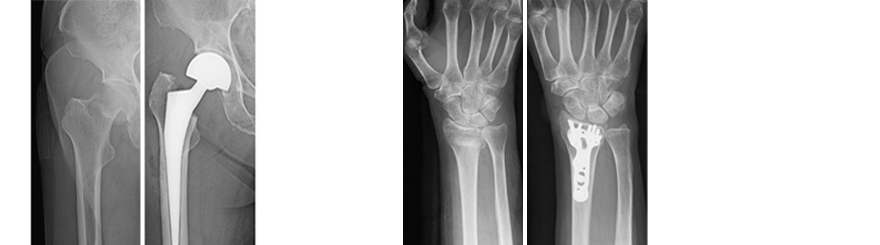

●大腿骨頸部骨折(人工骨頭挿入術後) ●橈骨遠位端骨折(骨接合術後)

●足関節骨折(骨接合術後)

●骨盤骨折(骨接合術後)